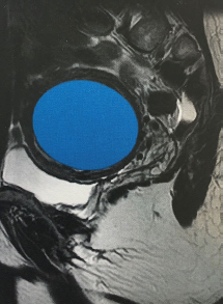

Están formados por células musculares y otros tejidos que crecen en y alrededor de las paredes del útero.

- Intramurales: crecen dentro de la pared muscular del útero

- Submucosos: crecen hacia el interior del útero y deforman su cavidad

- Subserosos: crecen y se proyectan hacia el exterior del úter